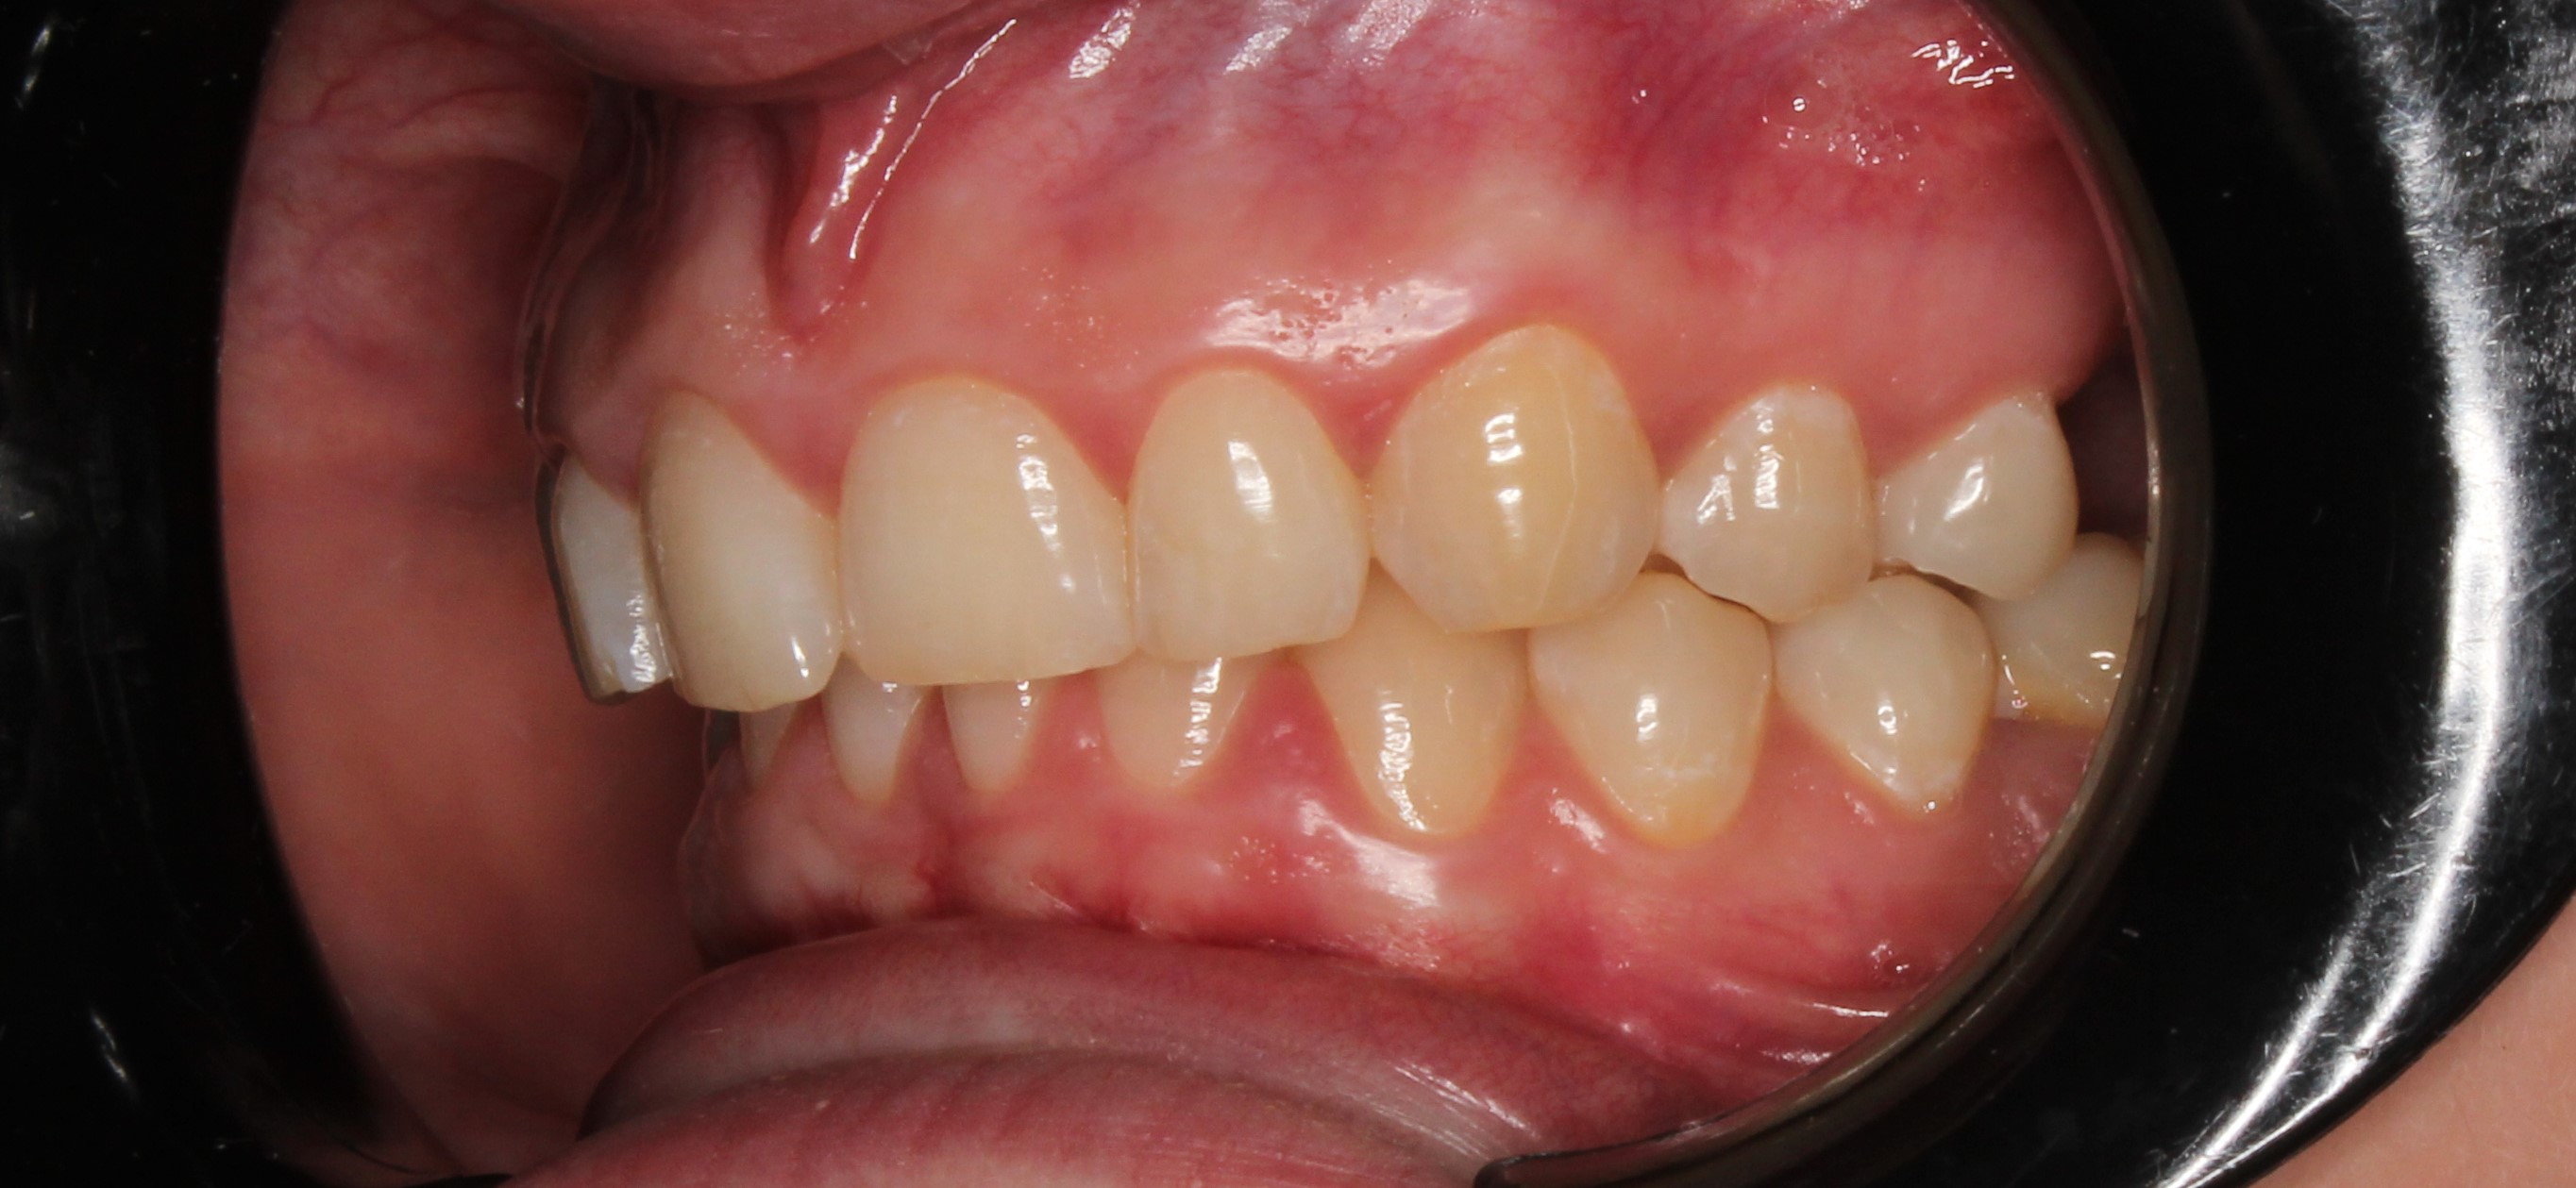

До и После: Лечение глубокого прикуса элайнерами

Лечение глубокого прикуса элайнерами. Начало лечения. Фиксация элайнеров